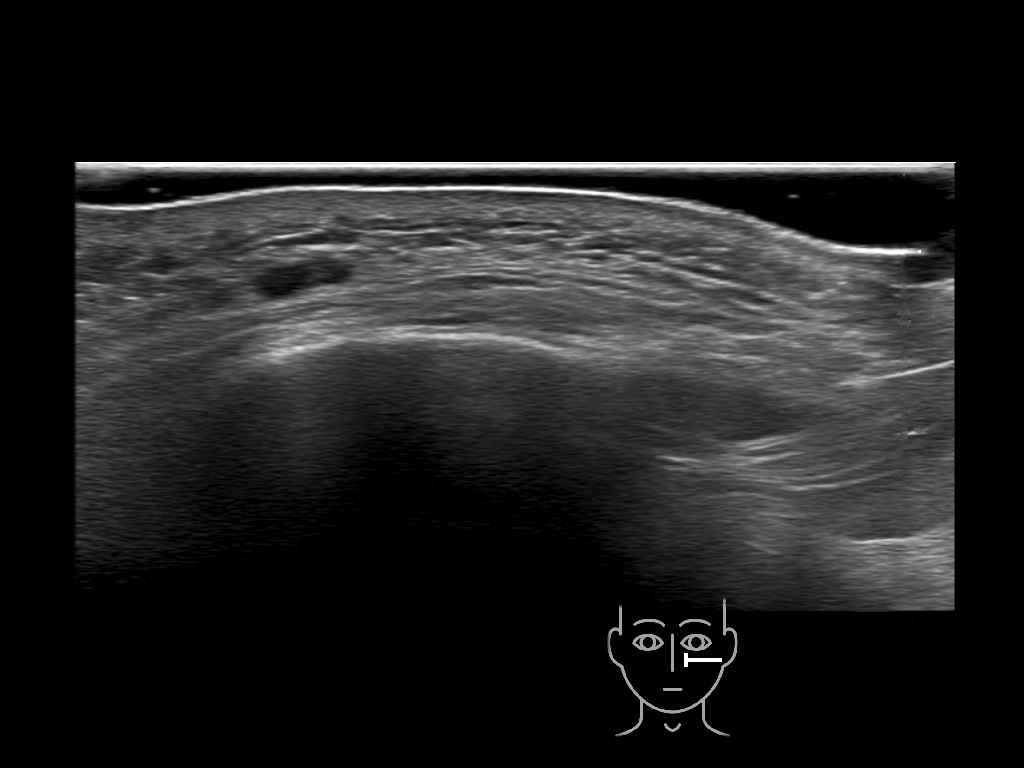

Filler deposits may end up unintentionally in the SMAS or fascial layers of the skin. Very often this will not lead to adverse events, however, adverse events ( nodules, migration / redistribution impaired muscle movement and smiling and malar edema) are are often related to filler ending up in the SMAS or fascia.

Study the first image to recognize the different layers. If you are sure about the layers, swipe to the second image to view the answer (if applicable).